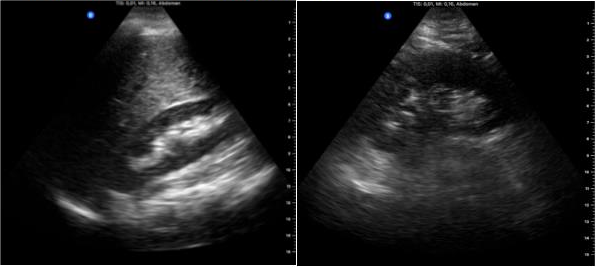

Segunda imagen: sonda convex. Izquierda, riñón izquierdo donde se objetiva el seno renal con dilatación de los cálices renales que confluyen parcialmente al igual que en el riñón derecho (imagen derecha).

Dada de alta con analítica normalizada y se repitió ecoscopia 10 días después del alta, objetivando resolución de las alteraciones de ambos riñones (imagen 3). Glucemias en rango con buena adherencia a medicación oral y 20UI de insulina.